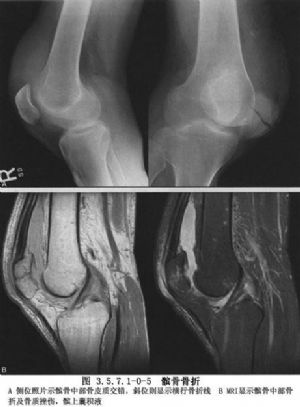

髌骨的解剖及髌骨骨折影像表现见下图(图3.5.7.1-0-1~3.5.7.1-0-10)。